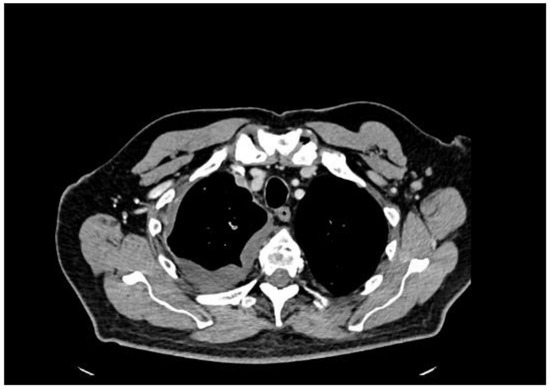

A 77-year-old man presented with several weeks of exertional dyspnea and intermittent dry cough. His past medical history was notable for ankylosing spondylitis, chronic gastritis, a left salivary gland tumor resected 11 years prior (pathologic details unknown), and a cholecystectomy. He had a significant smoking history (20 pack-years) but quit 32 years earlier. An initial chest radiograph, obtained to evaluate possible heart failure, revealed a large right-sided pleural effusion. Figure 1 A contrast-enhanced computed tomography (CT) of the chest further delineated multiple pleural nodules (up to 17 mm) and diffuse, bilateral small pulmonary nodules. Figure 2 and Figure 3 Two thoracenteses drained ~3800 mL of hemorrhagic pleural fluid in total. Fluid cytology was negative for malignancy, and no cell block preparation was performed. Further evaluation with bronchoscopy and bronchoalveolar lavage was unremarkable for infection or malignant cells.

Figure 3. CT—axial plane, after contrast administration, right-sided encysted pleural fluid and small enhancing after contrast administration pleural nodules.